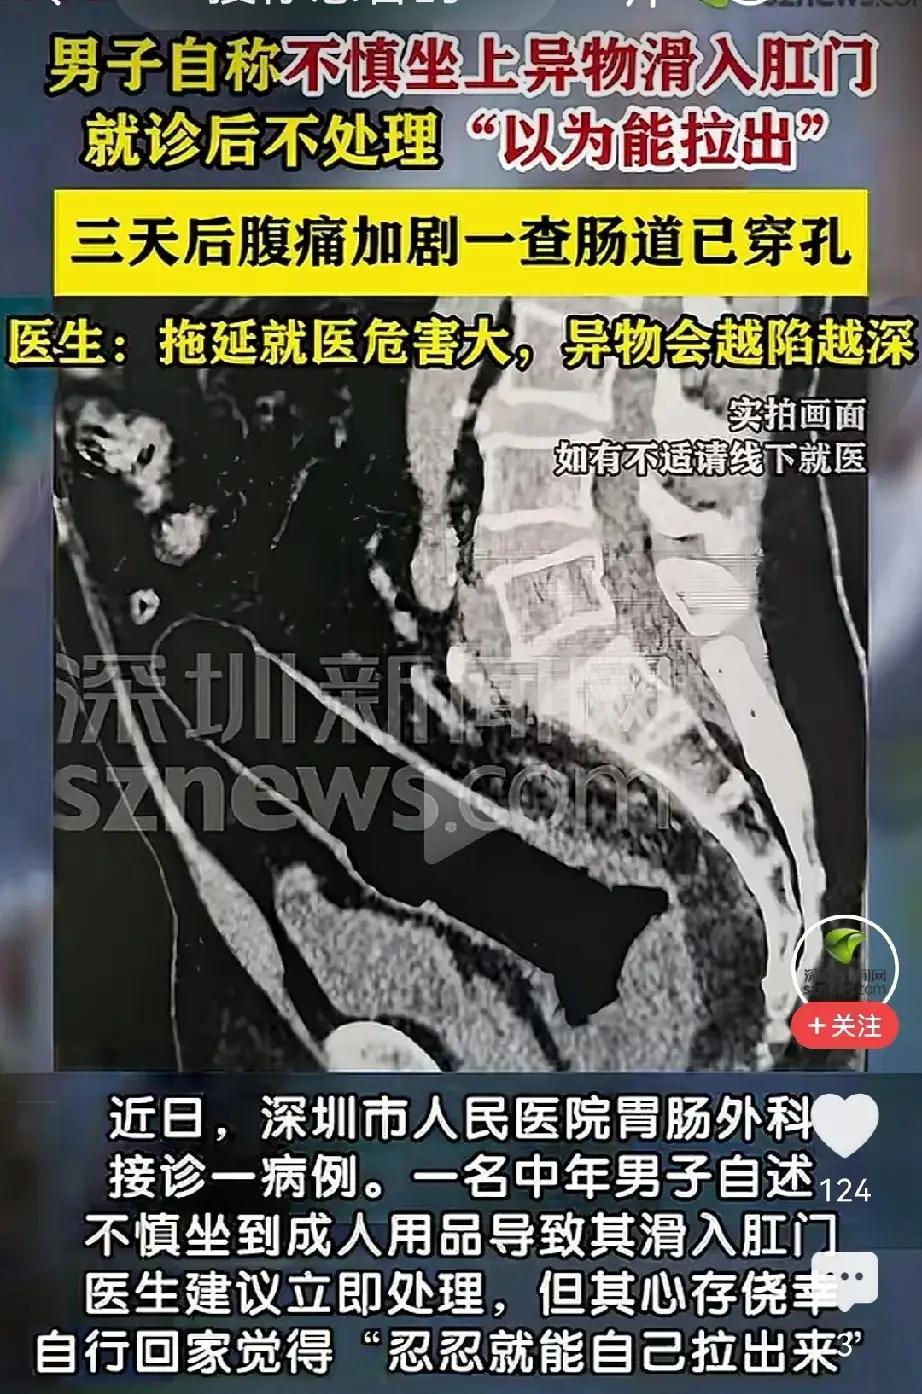

“菊花”失守72小时:一根网红“快乐棒”如何捅穿整条防线? 1️⃣ 急诊室凌晨3点的“社死”现场 值班护士小赵回忆:男子阿峰(化名)被推进来时,屁股垫着一次性护理垫,血渍外渗成一朵“玫瑰”。CT片上,一根20cm长、直径3cm的硅胶棒已戳破直肠,游离在腹腔——像一把倒插的“达摩克利斯之剑”。医生一句“怎么不早来?”让阿峰当场泪崩:“我以为是痔疮,忍忍就过了。” 2️⃣ 72小时“自救”全记录 • 第1天:异物塞入,肛门剧痛,他上网搜“如何自己抠出来”,结果只抠出更多血。 • 第2天:发烧38.5℃,灌肠、开塞露、筷子、镊子齐上阵,异物越捅越深。 • 第3天:肚子鼓成篮球,才想起打车去医院,却因“太尴尬”中途折返两次。 医生摇头:“再晚6小时,感染性休克直接进ICU。” 3️⃣ 网红玩具的“暗面” 同款商品详情页赫然写着“医用级硅胶、可全身水洗”,却找不到任何医疗器械备案号。评论区清一色“刺激”“秒到嗨点”,唯独缺一句“使用不当可能肠穿孔”。 更魔幻的是,客服自动回复:“亲,建议搭配润滑油哦~”至于润滑多少、深度几何?没人告诉你。 4️⃣ 医生给所有人的“菊花生存指南” ① 异物进入>5cm或无法自行排出,立即就医,别百度。 ② 任何“肛塞”玩具必须有底座或拉绳,防止“滑入失联”。 ③ 出现持续腹痛、发热、便血,就是穿孔前兆,挂急诊外科,别挂肛肠科排队。 ④ 带图问诊不丢人,丢人的是丢命。 5️⃣ 彩蛋:术后第5天,阿峰偷偷给护士站点了20杯奶茶 备注条写着:“替我谢谢医生,保住了我的‘第二张脸’。” 护士们把杯子排成一排,拍成“菊花守护联盟”打卡照。 评论区瞬间炸锅: “哥,你这一棒,捅开了多少人的羞耻盲区?” “奶茶我请,片子我绝对不看!” 留言区交给你: 如果朋友也遇到同款尴尬,你会陪他去医院,还是陪他继续“忍一忍”? 别害羞,评论区见真章!快乐自愈术 自制快乐法 快乐康复挑战